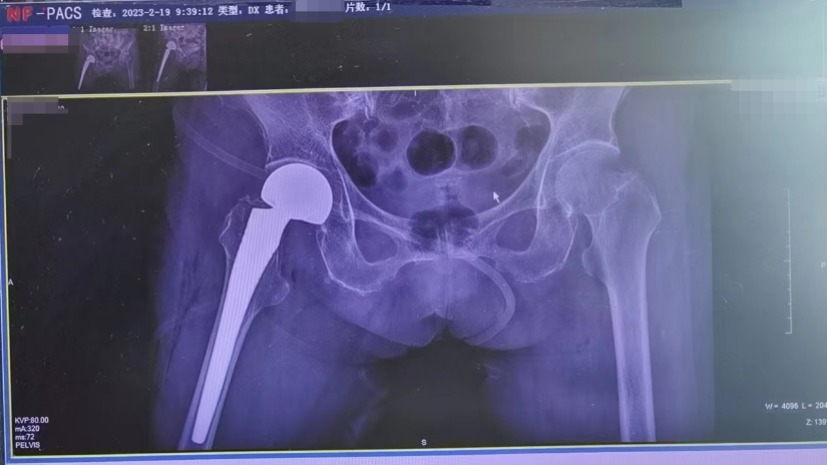

无独有偶,同一天髋关节二科杨小平主任医师手术团队也为另一位百岁患者黄奶奶做了人工关节置换手术,患者也是既往有高血压病史多年。入院诊断:1、右股骨颈骨折;2、高血压病3级 很高危组;3、2型糖尿病;4、腔隙性脑梗死;5、老年性心脏瓣膜病;6、老年性骨质疏松症;7、高血脂病;8、慢性胃炎。在椎管内麻醉下行右股骨颈骨折切开半髋关节置换术,手术半小时顺利完成,术中出血约150ml。黄奶奶术后第1天即可在家属辅助下坐起,第3天在助行器辅助下站立行走。近年来,该科做100岁老人的人工关节置换手术超10例。且效果良好。

▲术后拍片